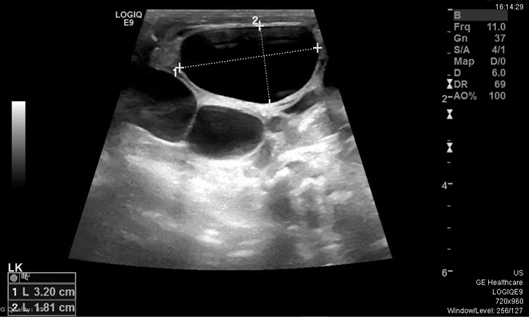

The initial examination showed small for age newborn, his growth parameters were all below 3rd centile donating intrauterine growth restriction. Grossly dysmorphic with wrinkled skin, flexed posture, abnormal head shape, high forehead, depressed nasal bridge anteverted nostrils, low set ears, micrognathia, proptosis, thick eyelashes and eyelids, partial syndactyly of 2nd and 3rd toes bilaterally with flattened feet and hands. The abdomen was bulging with palpable hard left upper quadrant mass, about 4cm, liver edge also felt below costal margin. The newborn was connected to mechanical ventilation for one day, extubated to CPAP, weaned to nasal cannula for another 3 days then he was off respiratory support till discharge. First x ray showed homogeneous soft tissue opacity occupying the left abdominal cavity pushing the bowel loops to the right side most likely the left enlarged kidney(Figure 1). Ultrasound scan revealed average size of both hepatic lobes with smooth surfaces, coarse hepatic parenchymal texture with diffuse periportal thickening, and extensive thick GB sludge. The Left Kidney was hugely enlarged Multicystic dysplastic with multiple sizable cortical cysts. It measures 6.7x3.8cm; right kidney was normal (Figure 2).

Figure 2 Ultrasound abdomen showing Hugely enlarged Multicystic dysplastic left kidney with multiple sizable cortical cysts.